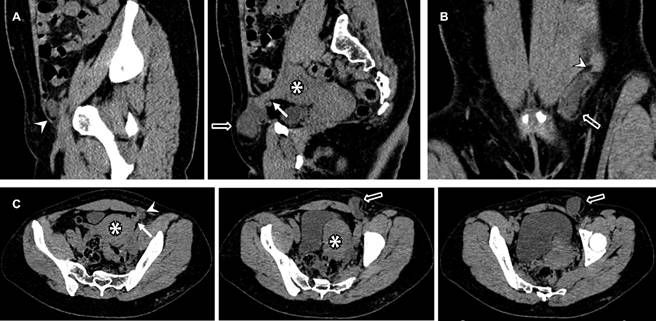

Una mujer de 45 años con antecedentes de dismenorrea e hiperpolimenorrea presentó dolor abdominal intenso y aumento de volumen en región inguinal izquierda. Los estudios de imagen revelaron una lesión hipoecoica en el ligamento redondo (Figura 1), sin aumento de vascularidad en el Doppler color y una imagen hipodensa en la tomografía (Figura 2). Se realizó una exéresis quirúrgica completa de la lesión sin complicaciones. Posteriormente, el resultado histopatológico reportó que se trataba de un foco endometriósico glandular.

Figura 2: Tomografía computarizada abdominopélvica en fase simple, con reconstrucción sagital (A), coronal (B) y cortes axiales (C). Se observa el útero en anteflexión lateralizado hacia la izquierda (*). En el nivel del canal inguinal (punta de flecha), se identifica una imagen hipodensa con valores de atenuación líquida (flecha hueca), la cual se extiende hacia el ligamento redondo ipsilateral (flecha recta).